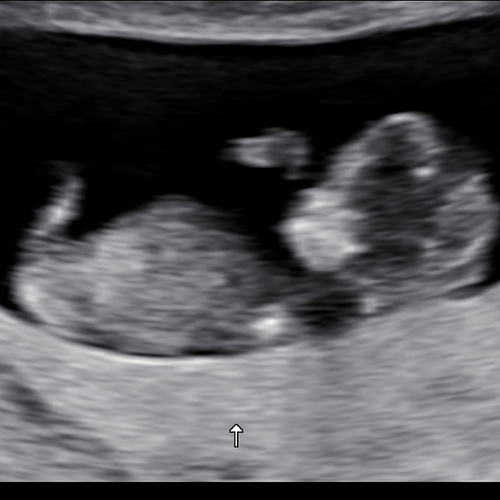

Jongen of een meisje? Wat denken jullie? 😁

Volgens mij zie ik een pipi 💙

Maar je bent zo'n 11w zie ik dus misschien dat het nog zakt. Of niet 😉

Wij hebben vrijdag de 20weken echo en dan hopen we ook te horen wat het wordt. Willen jullie alvast een gokje wagen om te zien of jullie gelijk zullen hebben? Dit was een echo van 16 weken